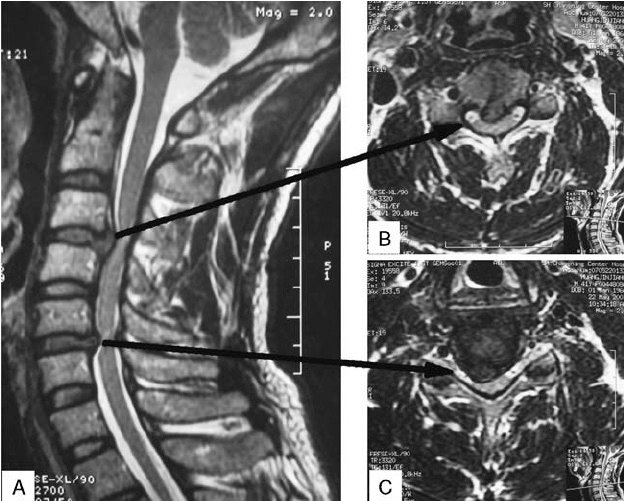

MRI scans of a male patient with cervical spondylosis at 2 noncontiguous levels with spinal cord compression at C3–C4 and C5–C6 due to disk herniation, and a normal C4–C5 disk. B, C, Transverse sections showing severe spinal cord compression due to disk herniation at C3–C4 and C5–C6. MRI indicates magnetic resonance imaging.